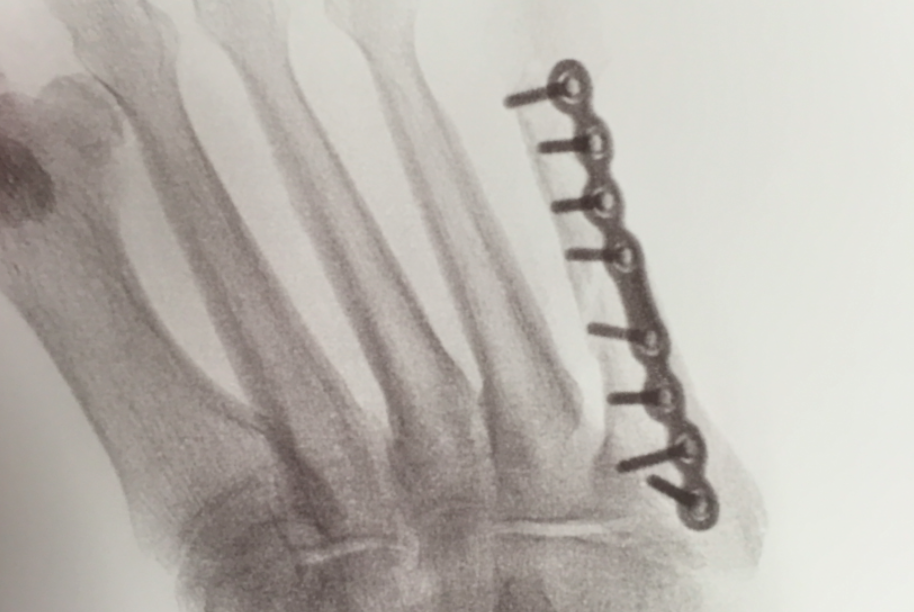

Fifth Met ORIF

5th Met Fx ORIF w VO